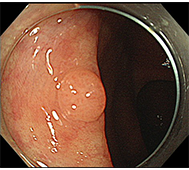

食道がん

初期症状は食道違和感や喉のつかえ感などの不定愁訴に近いため、発見が遅れやすく、食道がん自体がリンパ節転移が多いことや、周囲に浸潤しやすいことから、早く進行します。

- 内視鏡治療 :病変がリンパ節転移の無い早期食道がんに対し、内視鏡治療が行われます。